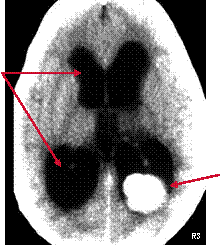

Hydrocephalus from Choroid Plexus Papilloma